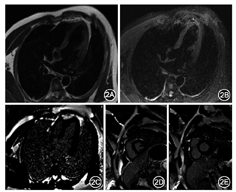

患者男性,31岁,菜贩。发热10 d伴关节痛3 d于2018年10月16日入院。入院前10 d受凉后出现发热、咽痛,入院前3 d出现左踝关节痛,随之双侧肩和肘关节疼痛,无呼吸困难和双下肢水肿,自测体温波动在38.5~39.2 ℃,以"发热待查"收入院。既往体健,12年前因外伤行脾脏切除术。家族史无特殊。体检:体温38.5 ℃,脉搏99次/min,呼吸20次/min,血压130/70 mmHg(1 mmHg=0.133 kPa)。无皮下结节,环形红斑,扁桃体Ⅱ度肿大,心肺查体无阳性体征,左踝关节红肿伴皮温升高。入院实验室检查:白细胞总数、红细胞沉降率(ESR)、C反应蛋白、抗链球菌溶血素均明显升高(表1),咽拭子未分离到A组β溶血性链球菌,尿常规、大便常规、肝肾功能、电解质、氨基末端B型利钠肽前体(NT-ProBNP)、心肌标志物、降钙素原、补体、免疫球蛋白、血培养等指标均正常。X线胸片和心脏彩色超声显示未见明显异常。心电图为窦性心律,Ⅰ度房室传导阻滞(atrioventricular block,AVB)。入院第5天心电图为窦性心律,完全性房室传导阻滞(complete atrioventricular block,CAVB)伴交界区逸搏,心率波动在33~45次/min(图1),无黑矇、晕厥。考虑发病前有受凉咽痛症状,满足急性风湿热(acute rheumatic fever,ARF)修订版琼斯标准中的1个主要标准和4个次要标准,临床诊断ARF,给予阿司匹林肠溶片(1.5 g,6 h 1次)、青霉素(320万单位,8 h 1次)、甲泼尼龙琥珀酸钠(120 mg,1次/d,3 d)治疗,糖皮质激素治疗后第2天,完善心脏磁共振检查(cardiac magnetic resonance,CMR)未见异常(图2)。积极抗风湿治疗后发热、关节痛明显改善,体温、血常规、C反应蛋白、ESR、抗链球菌溶血素指标逐渐恢复正常(表1),心脏节律由CAVB逐渐改善为Ⅱ度AVB、Ⅰ度AVB,最终恢复正常,出院后建议给予风湿热二级预防,每月肌肉注射长效青霉素持续5年。

病程中患者无心力衰竭症状,动态随访心肌损伤和心力衰竭标志物正常,心脏超声检查和CMR未见明显异常,提示心外膜、心肌、心内膜均未受累,风湿性心脏炎的诊断依据相对不足。本例患者仅表现为传导系统受损。组织学上,房室结-希浦系统被胶原结缔组织所包绕,与周围局部心肌组织绝缘,保证电激动的快速轴向传导[6],当心肌损伤时组织水肿可压迫传导系统发生传导阻滞。Carano等[7]对25例ARF导致CAVB的病例报道进行汇总分析,儿童占19例,CAVB致阿斯综合征有10例,CAVB的持续时间为数小时至3个月不等,最终有7例行永久性起搏治疗。本例患者在ARF急性期完善CMR检查,排除心肌炎症性水肿压迫传导系统的可能。基于上述分析,我们提出孤立性CAVB的可能病因是风湿性心脏传导系统炎,推测可能与特殊链球菌感染损伤传导系统相关。